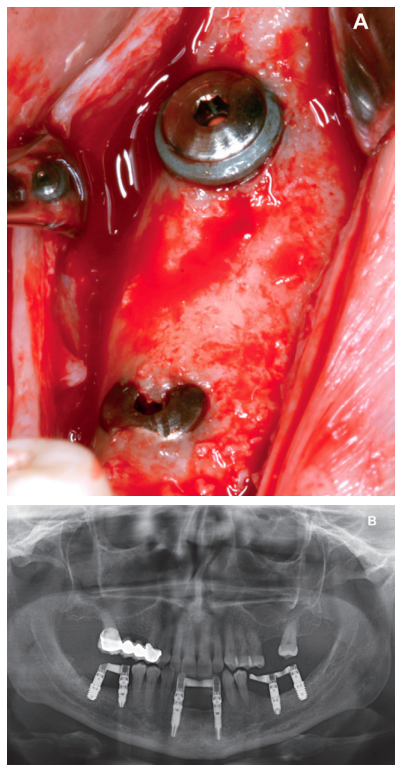

Currently in implant dentistry, we are increasingly faced with cases of extreme bone resorption that force us to implement different surgical dental implant techniques. The coexistence of vertical and horizontal atrophy makes successful resolution of these cases more difficult, as well as having to face these types of more complicated situations with increasing frequency, due to patients demanding implant treatment even in such very severe cases. It is not uncommon therefore to use combined techniques which include ridge expansion or short implants, for example. The following clinical case presented advanced horizontal and vertical alveolar atrophy in the right and left posterior regions of the mandible. The treatment plan included the use of short implants for the vertical atrophy and a two-stage alveolar ridge split to treat the horizontal atrophy.

Back in 2007, the therapeutic protocol for these cases was very different (Figures 5-7), with short implants without full development – and without studies demonstrating the importance of diameter over implant length – efforts were focused on the search for anchorage by implant length instead of looking for the bicortical (vestibular-lingual) stability that short and wide implants perform. During this ti me, the failure of molars 46 and 47 also occurred; these were also extracted and replaced with dental implants.

Aft er 4 years, the second and third quadrant molars began to have excessive mobility and serious periodontal problems, so it was decided to remove them and regenerate the alveoli with PRGF-Endoret. Once the area was regenerated (a month and a half later), a conebeam was performed to evaluate the residual bone volume. It can be seen how there was an uneven bone crest with areas of 3.3 mm in height up to a maximum of 7 mm (Figures 9 and 10). On this occasion, due to the protocol change described above, we opted for the direct insertion of extra-short implants, since the surgical protocols to address this type of situation in 2011 varied substantially, with these implants being a first-line tool for the treatment of this type of atrophy (Figure 11). Two extra-short implants were selected (5.5 mm diameter x 6.5 mm length for tooth 26, and 6 mm diameter x 5.5 mm length for tooth 27).